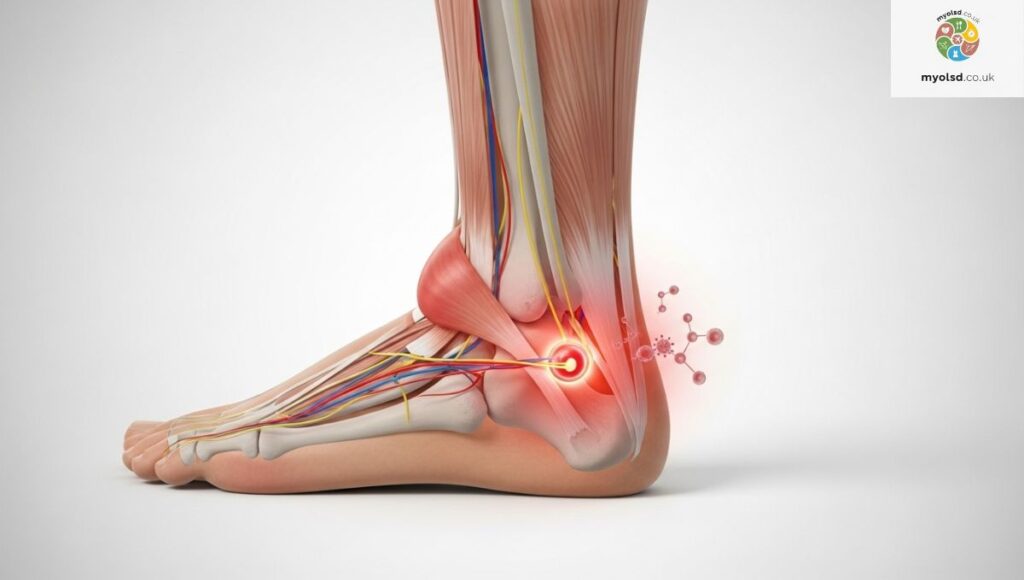

Ankles are complex joints made of bones, ligaments, tendons, and cartilage. This intricate structure allows for movement but also makes them vulnerable to injury and wear and tear.

When you’ve been lying still overnight, fluid can accumulate in the joints, tendons may tighten, and inflammation can increase, leading to that telltale stiffness when you first get up. Understanding your ankle’s anatomy helps you see why morning pain is so common.

What Causes Ankle Pain Without an Injury?

It’s common to wonder, “How can my ankle hurt if I didn’t injure it?” Conditions like reactive arthritis, bursitis, and autoimmune diseases often strike without a clear external cause.

Even poorly fitting shoes or prolonged pressure on your ankles while you sleep can contribute. This is why a thorough ankle evaluation, including diagnostic tests like X-rays, ultrasound, or CT scans, can be crucial.